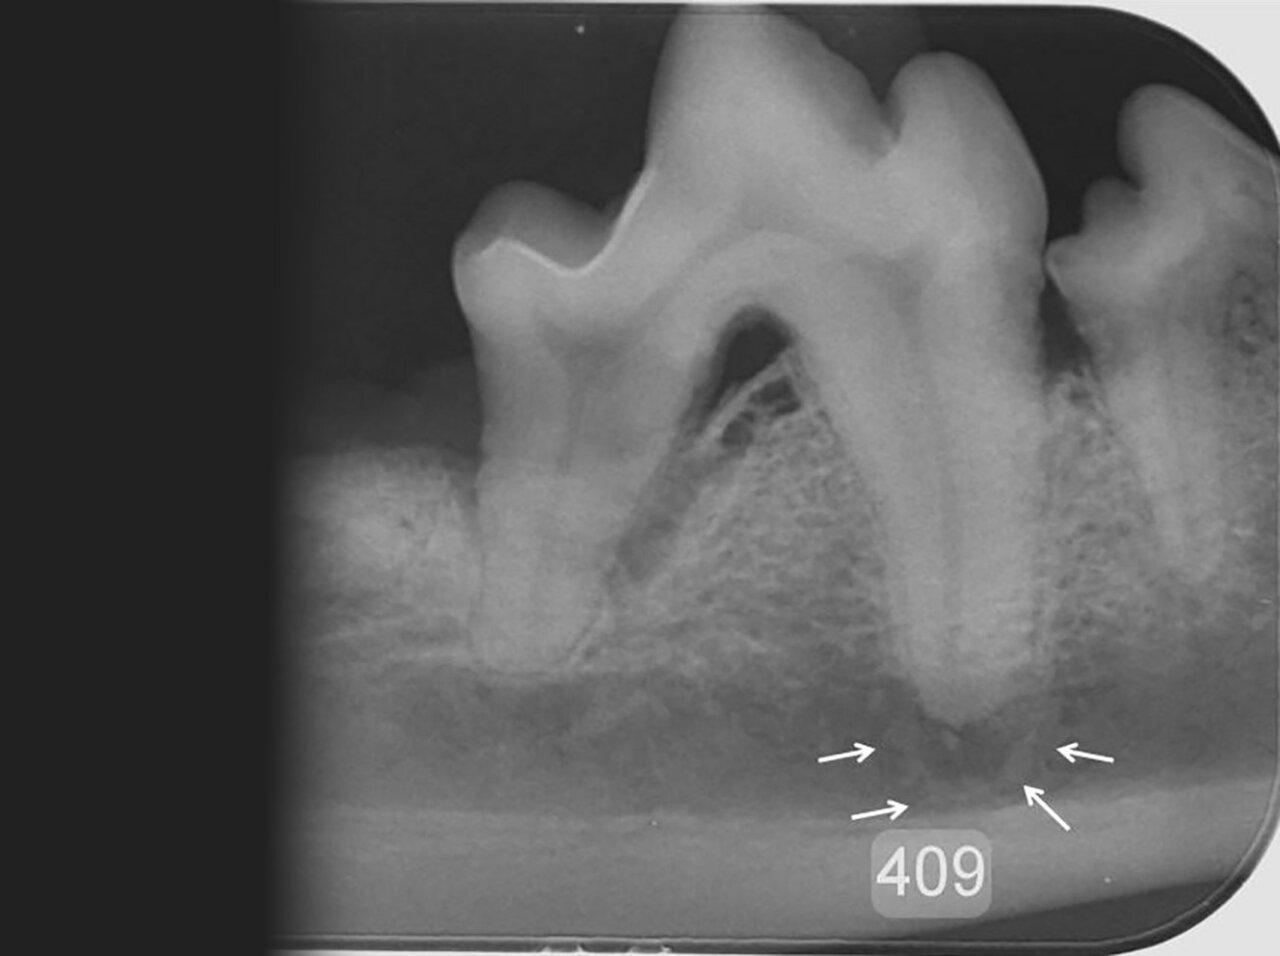

Para el diagnóstico de la EP, además de realizar un examen periodontal a través del sondaje debemos apoyarnos en la radiografía, ya que nos proporciona información acerca de la cantidad de pérdida ósea existente, así como del patrón que sigue esta pérdida (horizontal y/o vertical). En dientes multirradiculares, podemos servirnos de la furca para evaluar la pérdida de hueso, ya que aparecen áreas radiolúcidas bajo la bifurcación radicular a medida que se produce la destrucción ósea.

De acuerdo a esta pérdida del hueso alveolar detectada a nivel radiológico, clasificaremos la EP en cuatro grados:

- Grado 1 (PD1): sin pérdida ósea.

- Grado 2 (PD2): pérdida del soporte óseo menor al 25 % (imagen 7).

- Grado 3 (PD3): pérdida del soporte óseo de un 25-50 % (imagen 8).

- Grado 4 (PD4): pérdida del soporte óseo mayor de un 50 % (imagen 9).

Además de permitirnos evaluar el grado de enfermedad periodontal, también hace posible seleccionar el mejor tratamiento en función de su patología y las posibles complicaciones, como las fracturas mandibulares iatrogénicas en perros de talla pequeña con enfermedad periodontal PD4 (imágenes 10 y 11).